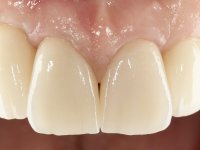

Após 5 anos da primeira intervenção, a paciente surge na consulta com uma peri-implantite nos implantes colocados no local dos dentes 1.2 e 4.6. Começamos por abordar a peri-implantite no local do dente 2.2. Foi feita uma ponte provisória de laboratório em acrílico com 2 elementos. O dente 1.1 como pilar e o 1.2 como pôntico, este último apresentava um apoio distal. A coroa do 1.2 foi removida do coto com um corte longitudinal feito com turbina e depois foi fraturada com um mini luxador. O coto foi de seguida desaparafusado do implante. Fez-se o mesmo procedimento para remover a coroa do 1.1. O dente 1.1 foi re-preparado e a ponte provisória foi rebaseada em boca com acrílico autopolimerizável. Feito o correto acabamento e polimento da provisória foi feita a sua cimentação temporária com cimento de policarboxylato. Numa consulta posterior. foi feita a remoção da ponte provisória, feita a cirurgia para explantação do implante, colocou-se um novo implante e fez-se a regeneração óssea da zona com uma membrana não reabsorvível. 3 meses após foi removida a coroa do implante colocado no 4.6. Foi feito um corte horizontal com turbina na zona cervical e com um mini luxador descolou-se a coroa do coto. Após este procedimento fez-se a explantação do implante. Após 6 meses foi colocado um novo implante no local do 4.6. Após a osteointegração foi feita a impressão com a técnica de moldeira aberta e foi confecionada em laboratório uma coroa aparafusada sobre o implante. Aprovada pela paciente foi apertada definitivamente em boca. Após 1 mês removemos a ponte provisória antero-superior, reforçamos o dente 1.1 com um poste intra- radicular e reconstruimos o coto com uma resina de polimerização dual. Nessa mesma consulta expomos o implante colocado no 1.2 e fizemos uma impressão pela técnica de moldeira aberta com silicone de dupla viscosidade e presa rápida. No laboratório foi feita uma ponte provisória de 2 elementos, aparafusada sobre o implante e cimentada sobre o dente. A primeira ponte provisória foi removida e colocada a segunda aparafusada sobre o implante. A linha de acabamento cervical do 1.1 foi rebaseada com resina composta durante o aperto do parafuso do implante. Depois foi removida, foram feitos os acabamentos e finalmente apertada sobre o implante e cimentada temporariamente sobre o dente. Após 2 meses de maturação dos tecidos moles em função do perfil de emergência criado pela nova ponte provisória, pudemos avaliar a estética conseguida em conjunto com a paciente. Neste longo processo o dente 2.1 teve que fazer um tratamento endodôntico. Decidiu-se assim fazer também uma coroa no dente 2.1.O dente 2.1 foi preparado na mesma consulta em que se fez a impressão ao implante. A ponte provisória foi utilizada para individualizar a peça de transferência, copiando o seu perfil de emergência e em seguida foi realizado o afastamento gengival com caolino. A impressão foi feita com a técnica de moldeira aberta com silicone de dupla viscosidade e presa rápida. Após a escolha da cor, a impressão foi enviada  para o laboratório onde foram confecionadas 2 coroas  com infraestrutura em Zr. revestidas a cerâmica para os dentes 1.1 e 2.1 e uma coroa aparafusada sobre o implante no dente 1.2. O trabalho final foi aprovado pela paciente e foi colocado definitivamente em boca. A coroa sobre o implante foi aparafusada com 35 N e as coroas foram cimentadas com cimento de ionómero de vidro reforçado com resina.